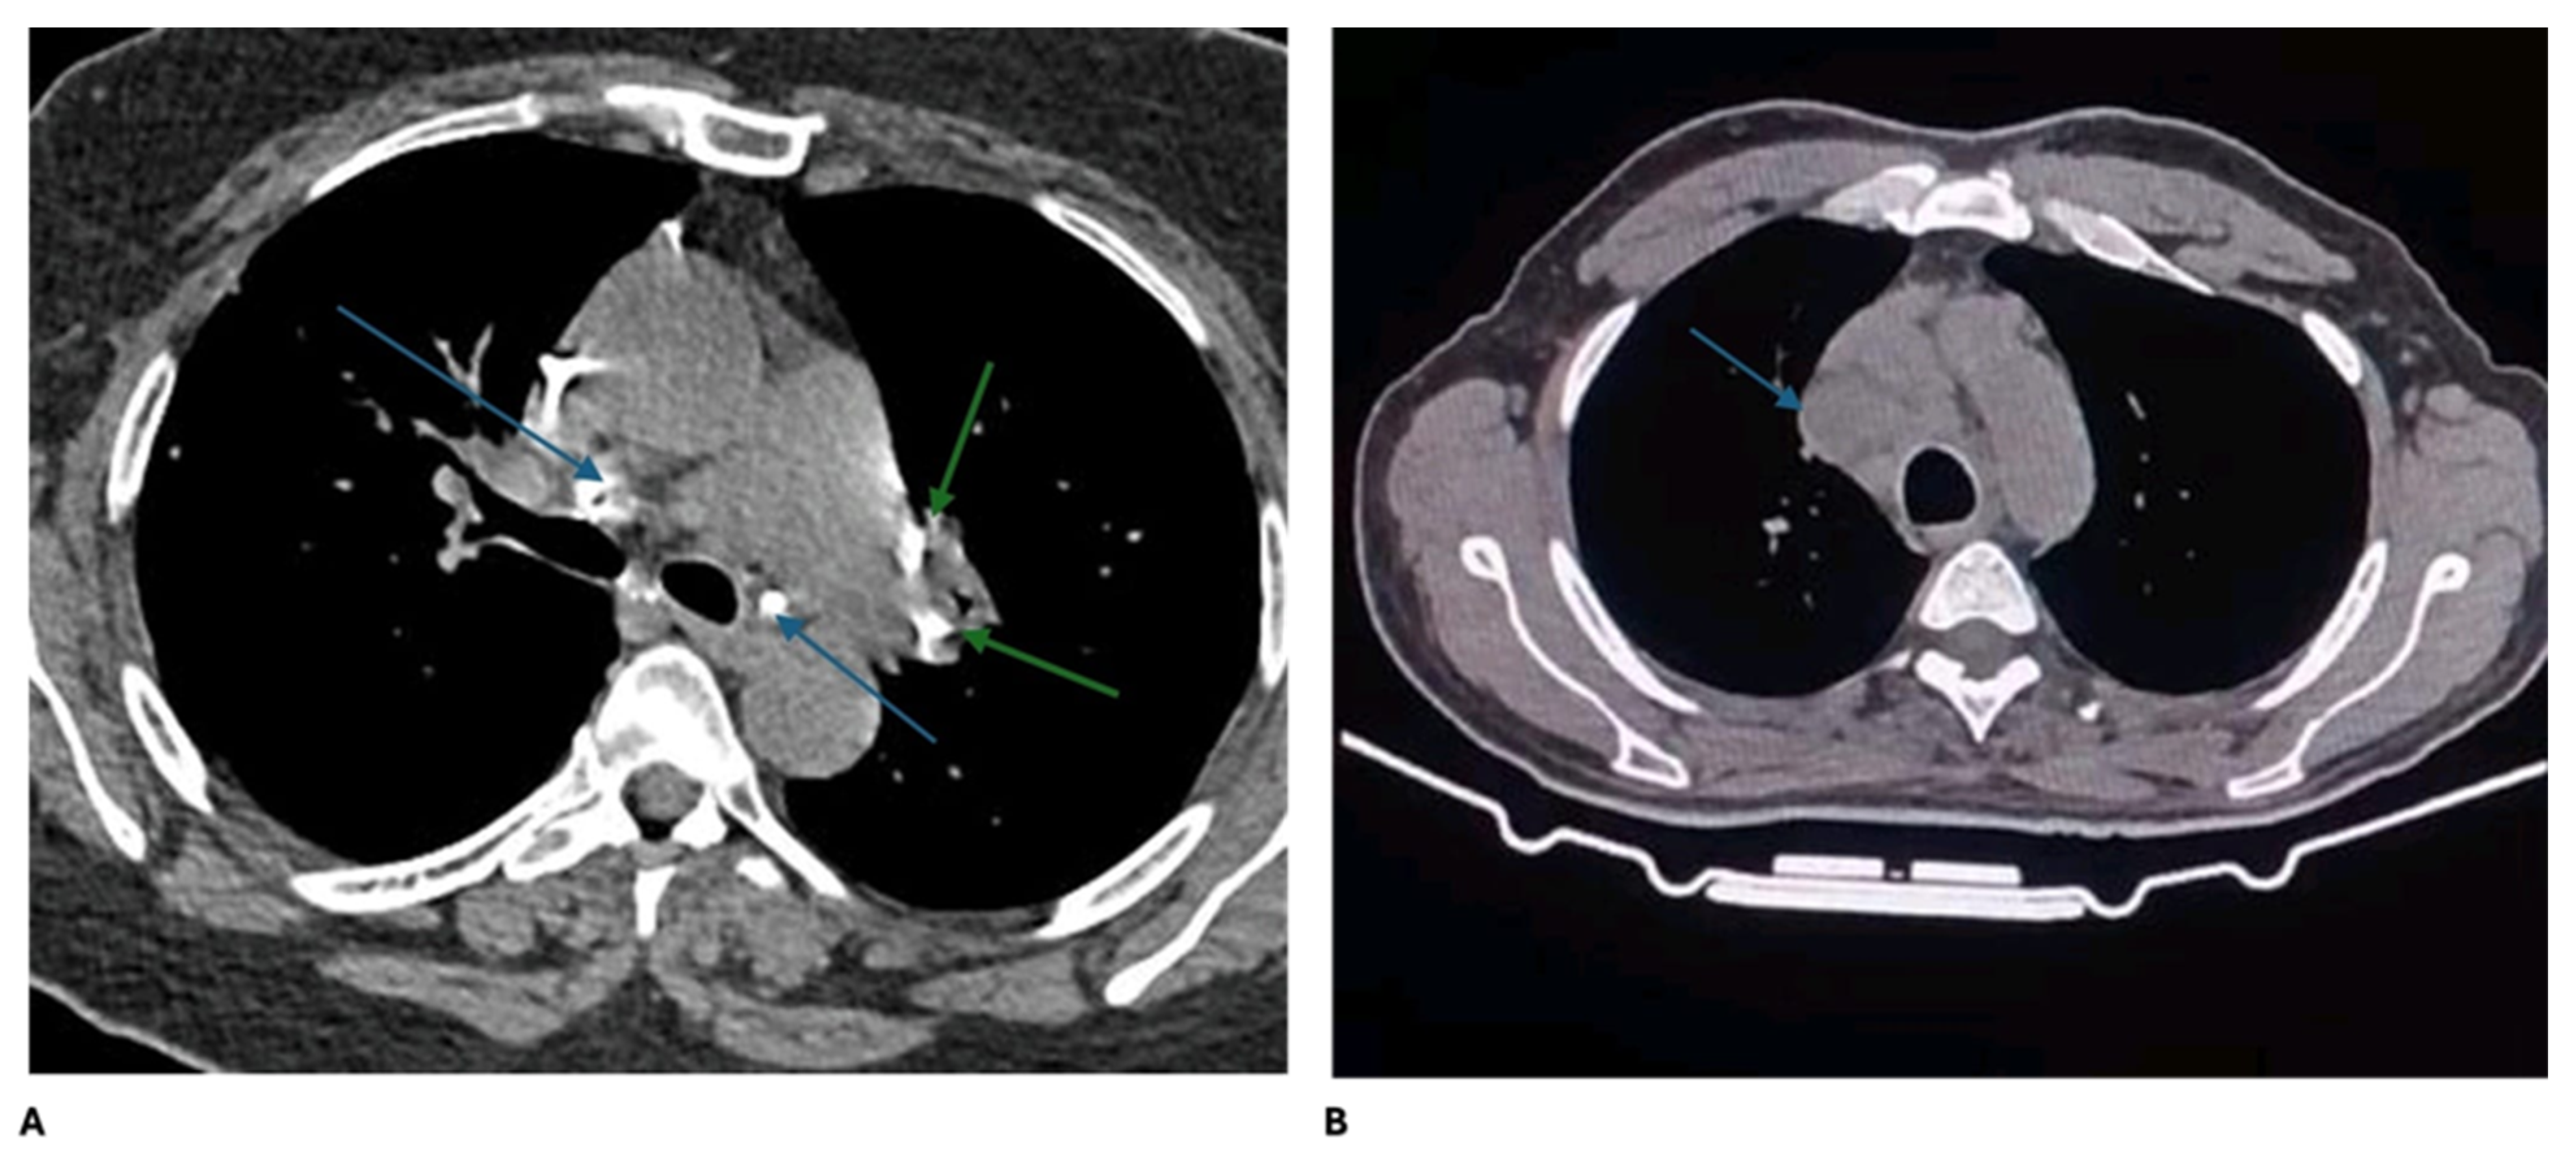

| Chest CT | χ2 | 0.083 | ||

| Calcified hilar and mediastinal lymphadenopathy | 6 (22.2) | 12 (44.4) | ||

| Non-calcified hilar and mediastinal lymph adenopathy | 21 (77.8) | 15 (55.6) | ||